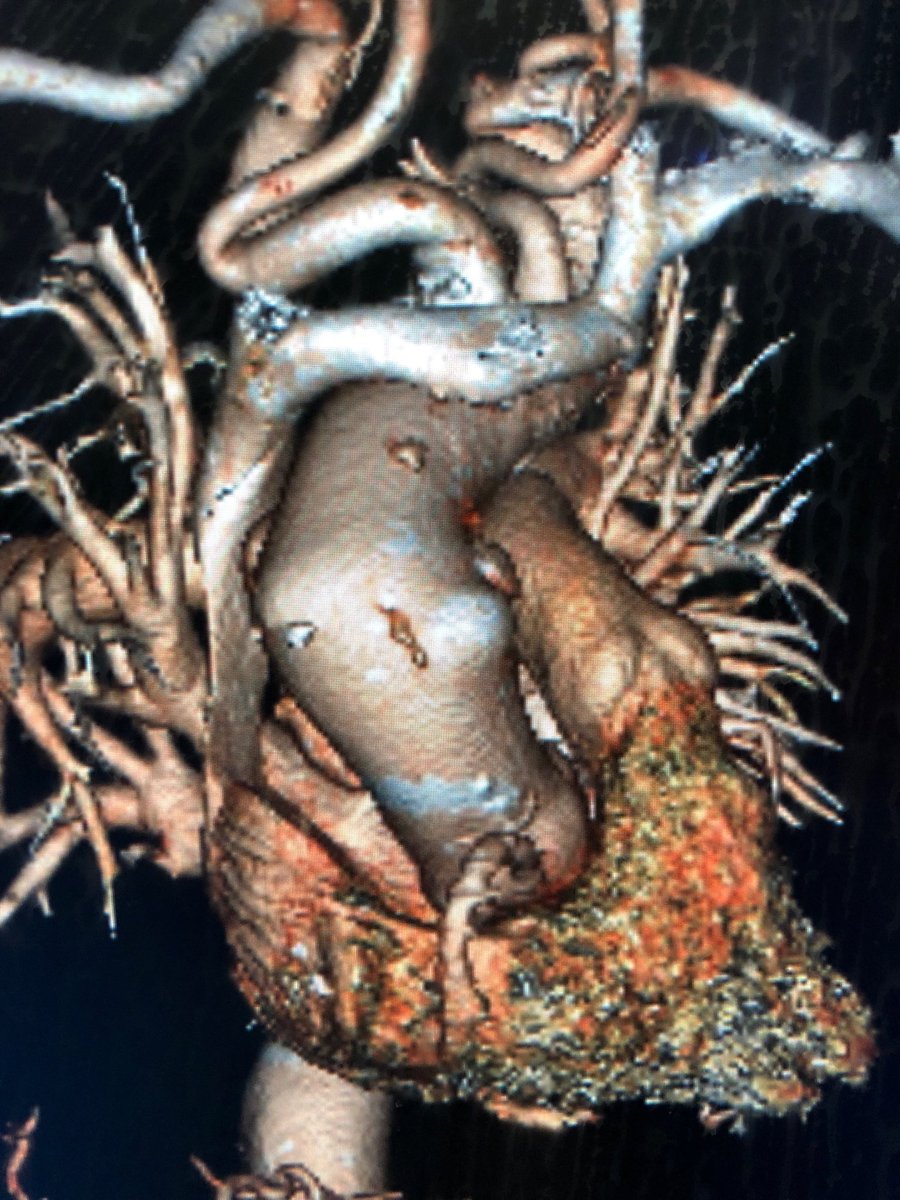

Great outcome using GORE TBE in an emergency case with replaced right SCA and zone 3 contained rupture PAU. Thanks to collaboration of Vascular and Cardiac surgery team. @MarylandSurg @UMMC The first commercial use of TBE in Maryland

@SToutsavadkohi @dr_ghoreishi @BtaylorMD2

Emergency #TEVAR for #ruptured #typeA #dissection and #aneurysm in #nonagenarian. 1 year follow up #CT shows #healed #aorta #VascularSurgery @CedarsSinai